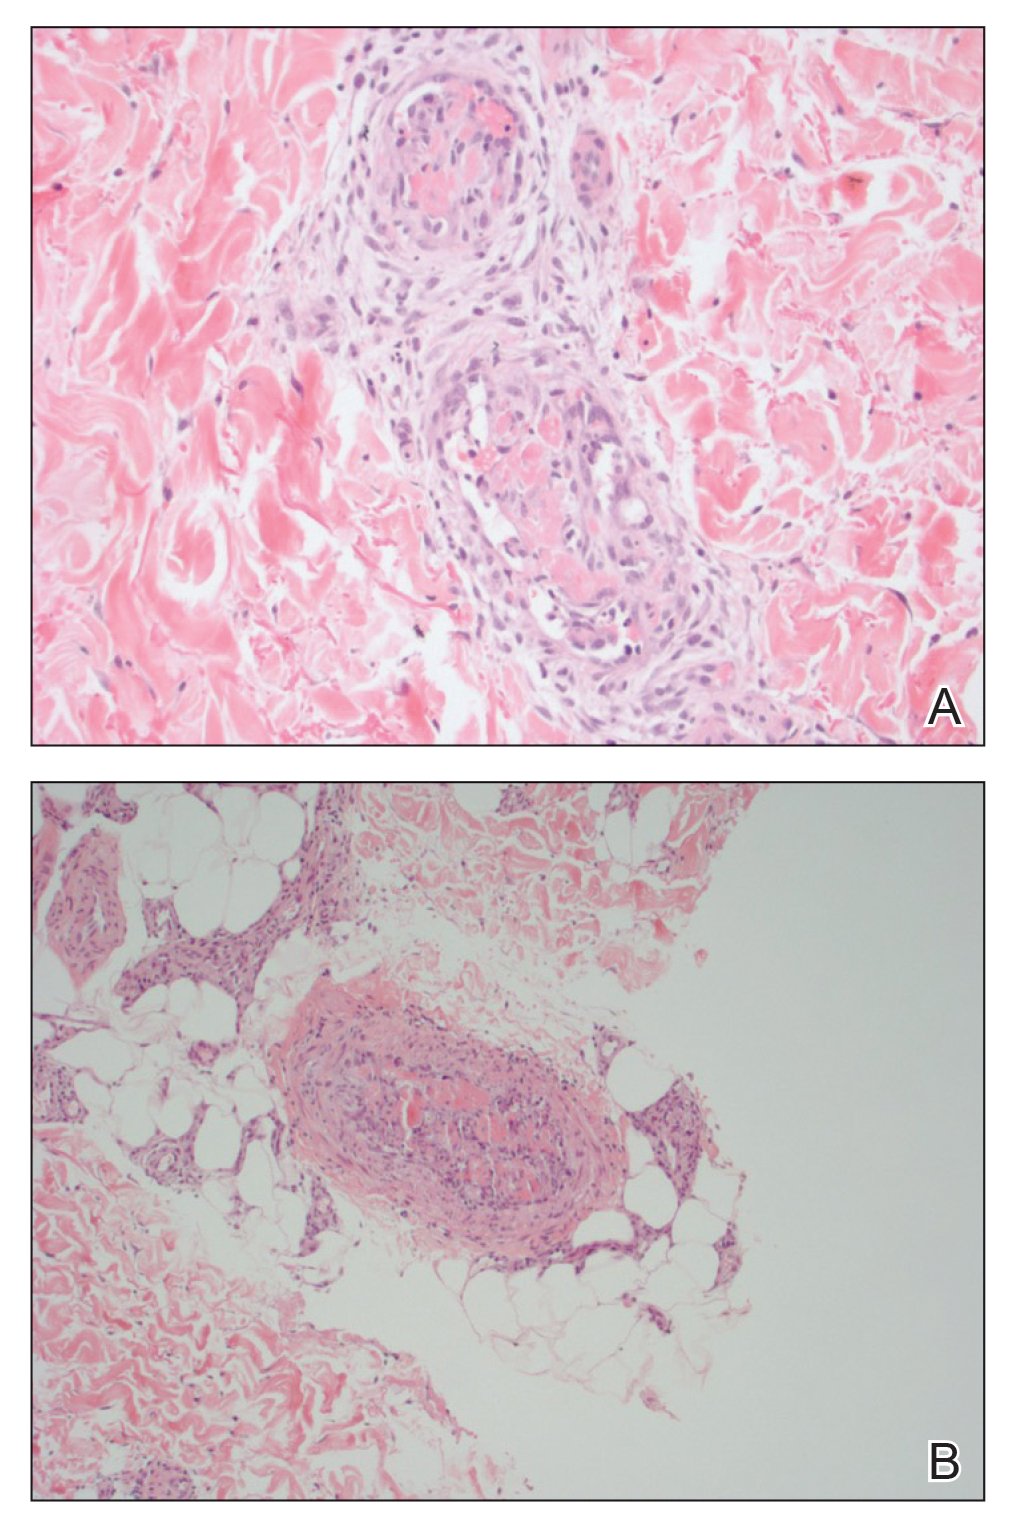

Coagulation studies and white blood cell counts were within reference range. A urine toxicology screen was positive for cocaine; however, urine testing for levamisole was not performed given the short half-life of levamisole in vivo. A biopsy of one of the skin lesions on the right thigh showed pauci-inflammatory superficial and deep vein thrombosis with recanalization (Figure 2). A rheumatology workup revealed an elevated C-reactive protein level, low C3, positive antinuclear antibody, positive anti–double-stranded DNA, positive anticardiolipin antibody, positive lupus anticoagulant, and positive perinuclear antineutrophil cytoplasmic antibody (ANCA). Tests for HIV, hepatitis B and C, cryoglobulinemia, and cytomegalovirus were negative. Given the clinical picture and laboratory findings, levamisole-induced vasculitis was deemed likely. The patient was treated with appropriate skin and wound care. She was discharged with a prednisone taper and oral cephalexin and was counseled on cocaine cessation.

Five months later, the patient was readmitted for lower extremity edema and worsening painful lesions that had progressed to involve the legs, thighs, buttocks, flanks, and the tip of her nose. A deep vein thrombosis workup was negative. She admitted to ongoing cocaine use that was confirmed with urine toxicology. Coagulation studies and white blood cell counts remained within reference range. Repeat skin biopsy was consistent with prior findings, demonstrating thrombosis of superficial and deep vessels with recanalization. In addition, it showed focal epidermal necrosis and a perivascular infiltrate of lymphocytes, histiocytes, and rare neutrophils. She was placed on high-dose methylprednisolone. Over the course of the next month, her urine continued to test positive for cocaine, and she developed necrotizing fasciitis necessitating lower extremity amputation, abdominal washout, and debridement. She quickly deteriorated, developing multiorgan failure with sepsis, leading to death. Of note, the patient was never found to have neutropenia or agranulocytosis throughout the disease course.

The pathogenesis of LIV is not completely understood, but it is thought to be an immune complex–mediated process based on immunofluorescence studies in the skin.13,14 Classic pathologic findings include multiple fibrin thrombi within small vessels in the superficial and deep dermis, leukocytoclastic vasculitis of small vessels consisting of fibrinoid necrosis of the vessel wall, extravasated erythrocytes, karyorrhectic debris, and angiocentric inflammation.14 Direct immunofluorescence is not routinely performed but most commonly demonstrates deposition of IgA, IgM, and C3.14,15